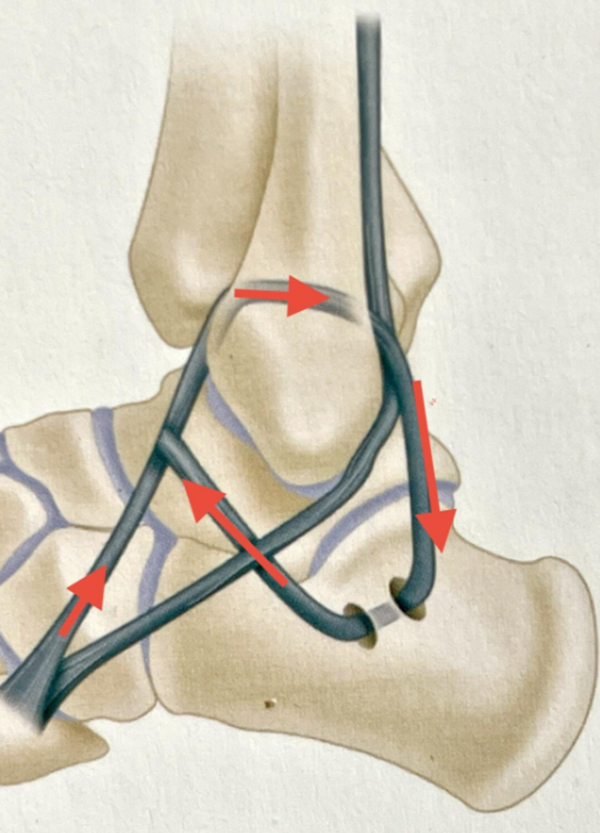

3、Chrisman-Snook术式(改良Elmslie手术)

1/2腓骨短肌腱重建距腓前韧带和跟腓韧带,同时加强踝关节和距下的稳定性。

在外踝后上2cm腓骨后缘纵行切口,保护腓肠神经,显露腓骨长肌将其向后牵开,辨认腓骨短肌腱的腱腹交界处,腓骨短肌腱劈开一半,向上至腱腹交界处切断返折。

远端J切口,保护腓浅神经及腓肠神经,切开腓骨长短肌腱鞘,向后牵开腓骨长肌腱,继续游离劈开的腓骨短肌腱至第五跖骨基底附着处。

在腓骨上靠近胫腓关节从前向后钻一个大小适宜的骨隧道。缝线编织缝合腓骨短肌腱远断端,移位肌腱从前向后穿过骨隧道,维持踝关节于中立位和足轻度外翻位。

(1)重建距腓前韧带:

拉紧肌腱,2-0韧带线将肌腱缝合于钻孔出口前端临近的骨膜组织,用移植肌腱重建距腓前韧带。

若距骨上距腓前韧带仍有残端,将其牢固缝合于移植肌腱。

图10 移位肌腱从前向后穿过骨隧道,重建距腓前韧带

向远后侧显露跟骨的外侧缘,剥离骨膜显露跟骨外侧垂直方向的骨突。在骨突的前后部间隔1.5cm分别钻一个与腓骨钻孔大小相同的孔,用弯刮匙刮通两孔形成骨隧道。

(2)重建跟腓韧带

移植肌腱从后向前穿过跟骨隧道,移位肌腱与骨隧道两端临近骨膜软组织缝合。移位肌腱从腓骨沿后下方向重建至跟骨,与跟腓韧带走行一致,重建跟腓韧带。

或在跟骨预定钻孔处锚钉固定缝合移位的腓骨短肌腱。

腓骨短肌腱游离端较长可以将其反折至腓骨孔道前端与腓骨短肌腱自身缝合。

(5)Chrisman-Snook术式(改良Elmslie手术)示意图

图13 肌腱移植方向